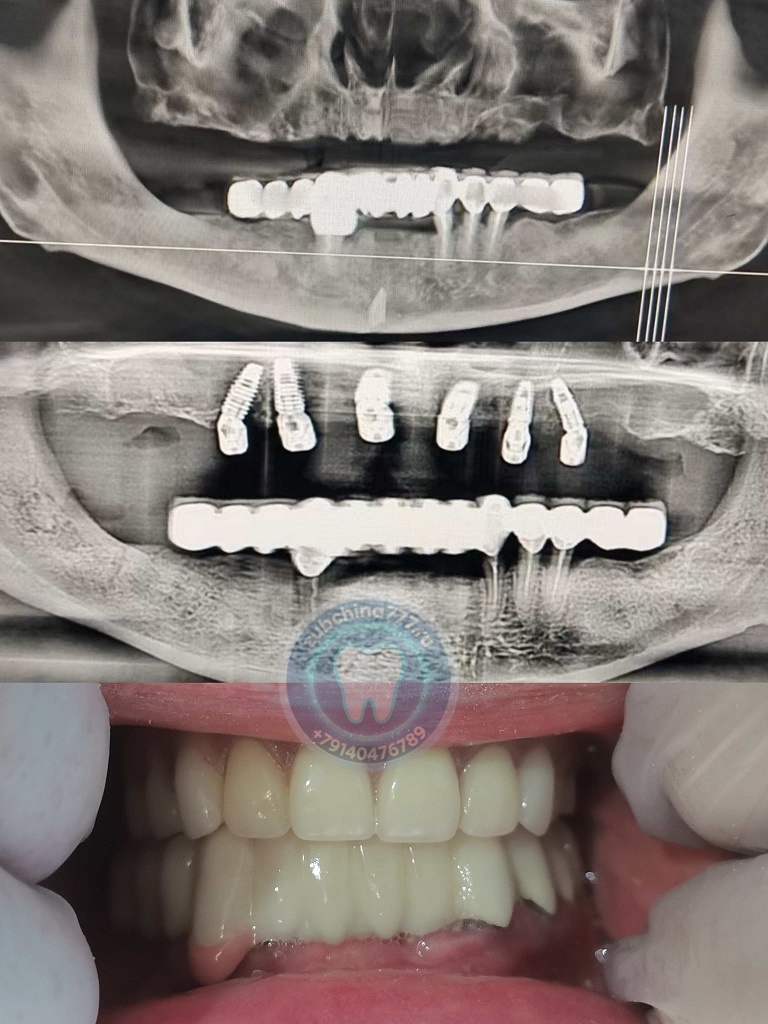

Фотографии пациентов ДО и ПОСЛЕ лечения и протезирования зубов в Хэйхэ